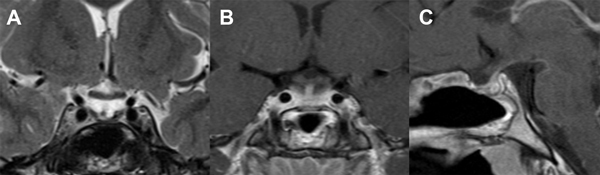

Figura 1. A: IRM T2 coronal en la que se visualiza tumor selar con desplazamiento del quiasma óptico. B y C: IRM T1 coronal y sagital con gadolinio que muestran centro hipointenso con captación periférica en anillo.

Paciente de sexo masculino de 17 años de edad, sin antecedentes de relevancia, que consultó a la guardia del hospital por presentar fiebre, cefalea intensa y vómitos de 48 horas de evolución. Al examen neurológico se encontraba lúcido, sin alteración de pares craneales, sin déficit motor ni sensitivo y presentaba rigidez de nuca. Se interpretó el cuadro como un síndrome meníngeo, por lo que se realizó un análisis de sangre que evidenció leucocitosis leve, una tomografía computada (TC) de encéfalo informada como normal y una punción lumbar. El examen físico-químico del LCR evidenció un color cristal de roca, 1425 células/mm3 con predominio mononuclear, glucorraquia de 53 mg/dl (glucemia de 102 mg/dl) y proteínas de 110 mg/dl, interpretándose como una meningitis, iniciándose tratamiento antibiótico y antiviral empírico. La serología para HIV y VDRL fueron negativas. Los cultivos de LCR fueron negativos para gérmenes comunes, micobacterias y hongos, así como también el panel viral, por lo que se interpretó como una meningitis aséptica. Se completó estudio con imagen por resonancia magnética (IRM) de encéfalo que evidenció una lesión expansiva selar con extensión supraselar de 14 x 16 mm de diámetro, quística, hipointensa en T1, levemente hiperintensa en T2, sin restricción en secuencia de difusión, con refuerzo periférico tras el contraste, con compresión y deformidad del quiasma óptico (Fig. 1). Tras este hallazgo, se realizó un campo visual computarizado que fue normal y se plantearon diferentes diagnósticos diferenciales: quiste de la bolsa de Rathke, craneofaringioma y adenoma quístico. El panel hormonal no evidenció alteración de la función hipofisaria y el paciente no refería trastornos en el crecimiento, ni en la libido, ni tampoco signosintomatología de diabetes insípida u otra alteración hidroelectrolítica. Tampoco se evidenciaron calcificaciones de la lesión en la TC. Se discutió el caso y se decidió la conducta quirúrgica.